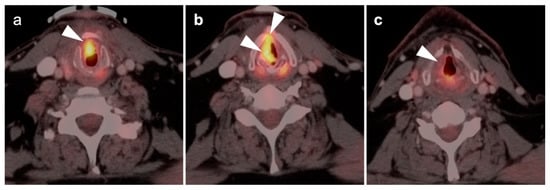

2.6. Thyroid Cancer

- Anaplastic thyroid cancer

- 4.

- Medullary thyroid cancer